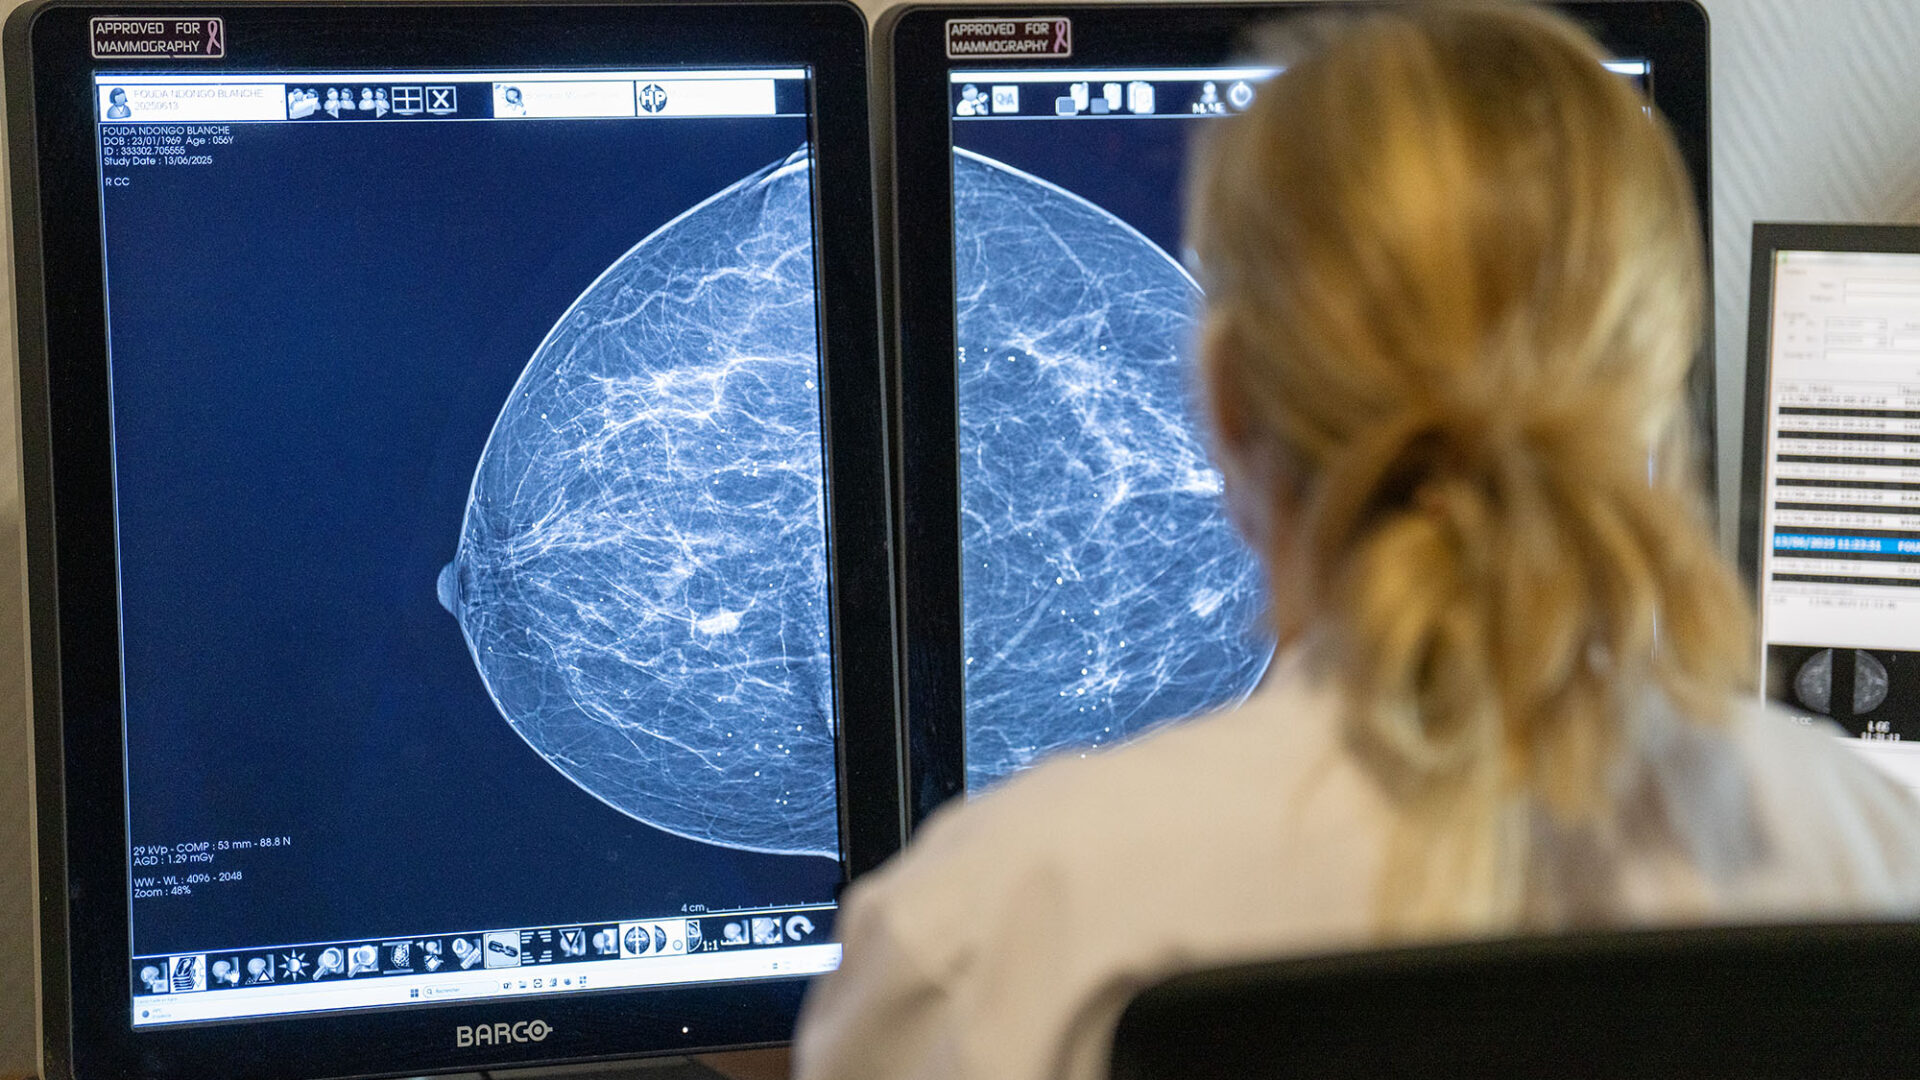

Le service de Cancérologie de la Polyclinique Bordeaux Nord dispose depuis plus de 20 ans d’un service de Recherche Clinique avec 4 attachées de Recherche Clinique et une infirmière dédiée.